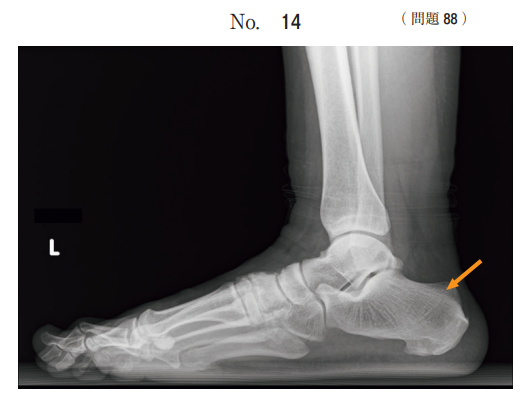

午後/問題88

足部の X 線写真(別冊No. 14)を別に示す。

矢印で示すのはどれか。

1.距 骨

2.脛 骨

3.踵 骨

4.舟状骨

5.立方骨

答え

3